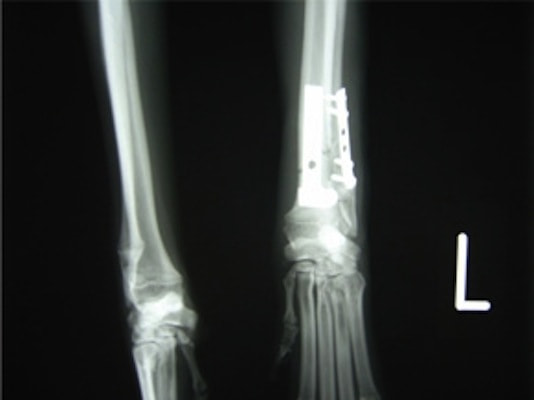

トイプードル 右遠位橈尺骨短斜骨折のALPSによる内固定

LCPは、スクリュー(ネジ)とプレート(金属の板)をロックする特殊な構造により骨折部位を固定する新しい世代のプレートシステムです。ひとつのホールでロッキングスクリューとスタンダードスクリューの使用を選択できるユニークな構造をしているため、骨折断端間の圧迫を目的とした従来型プレート固定法に加え、高い角度安定性を有するロッキングスクリューを用いた固定法の選択が可能です。従来のプレートシステムでは困難だった部分の骨折や癒合不全の症例に高い治療効果をもたらします。

7.1.5mmと薄いプレートのため、超小型犬にも使用しやすい